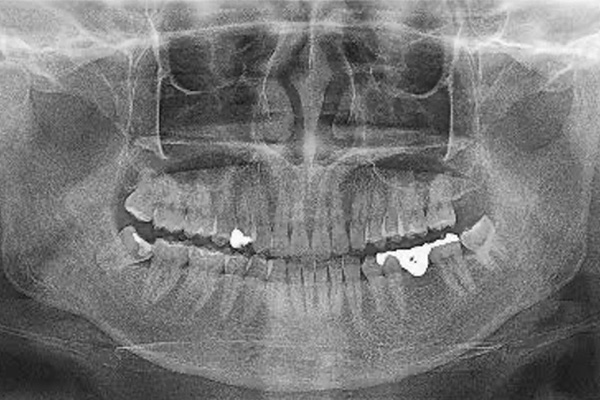

親知らず

手前の歯の虫歯、歯周病を引き起こすデメリットがあります。

そのリスクを解消するためには抜歯が必要です。